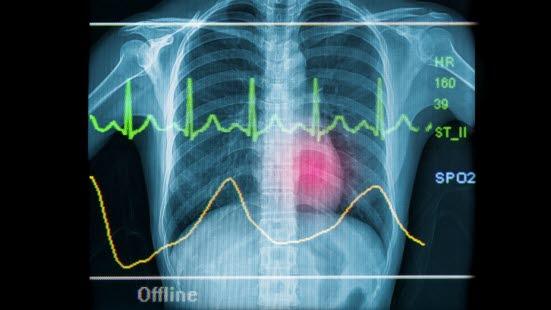

EKG ved angina og hjerteinfarkt

Ved angina er hvile-EKG normalt. Ved hjerteinfarkt derimot viser EKG unormale forandringer i hvile.

EKG viser et typisk mønster som for ett hjerteslag består av en P-bølge, et QRS-kompleks og en T-bølge. Siden et EKG kan registere mange etterfølgende hjerteslag, ser man på EKG-opptakene et regelmessig mønster av disse elektriske utslagene.

Når et område av hjertemuskelen har for dårlig blodtilførsel, gir det forandringer på EKG. Det synes i den delen av EKG'et som betegnes ST-segmentet. Oksygenmangel i et område av hjertemuskelen vil vises som et senket ST-segment. Ved å granske hvilke avledninger ST-senkningen forekommer i, kan man si hvor omtrent problemet sitter og kanskje også hvilken koronararterie som er trang.

Ved hjerteinfarkt vil et område av hjertemuskelen dø og etter hvert erstattes med bindevev som er uten evne til å bidra med kraft til sammentrekningen av hjertet (se illustrasjon av hjerteinfarkt). Denne skaden av hjertet gir flere forandringer på EKG. Den første forandringen som observeres, er at ST-segmentet blir hevet. Dernest kan det dannes en ny Q-bølge. Senere kan man observere at T-bølgen snur (blir invertert) - i stedet for å gå oppover går den nedover. Mens ST-forandringene er forbigående, er forandringene i Q- og T-bølgene som regel varige, og de kan brukes til å påvise "gamle" infarkt. Akkurat som ved angina pectoris kan legene ved å konstatere i hvilke avledninger forandringene forekommer, fastslå hvor i hjertet infarktet er.